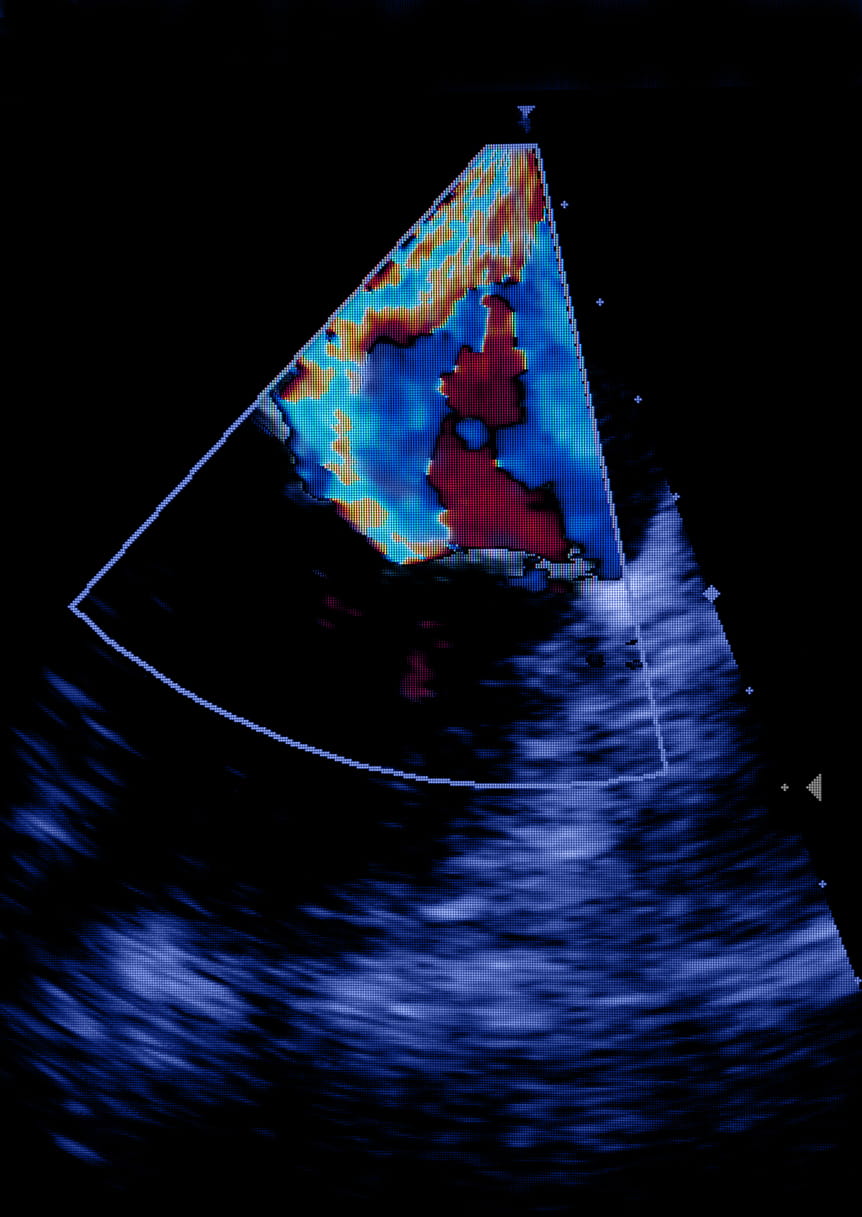

In the operating room and with Leah asleep, the team worked together, threading a tiny, fabric-covered metal clip through a puncture in the femoral vein in Leah's leg and up to her heart using a tube called a catheter. Using ultrasound and X-ray to guide them, they positioned the clip directly at the area where the mitral valve was leaking and then released it, pinning the two leaflets together and reducing the regurgitation.